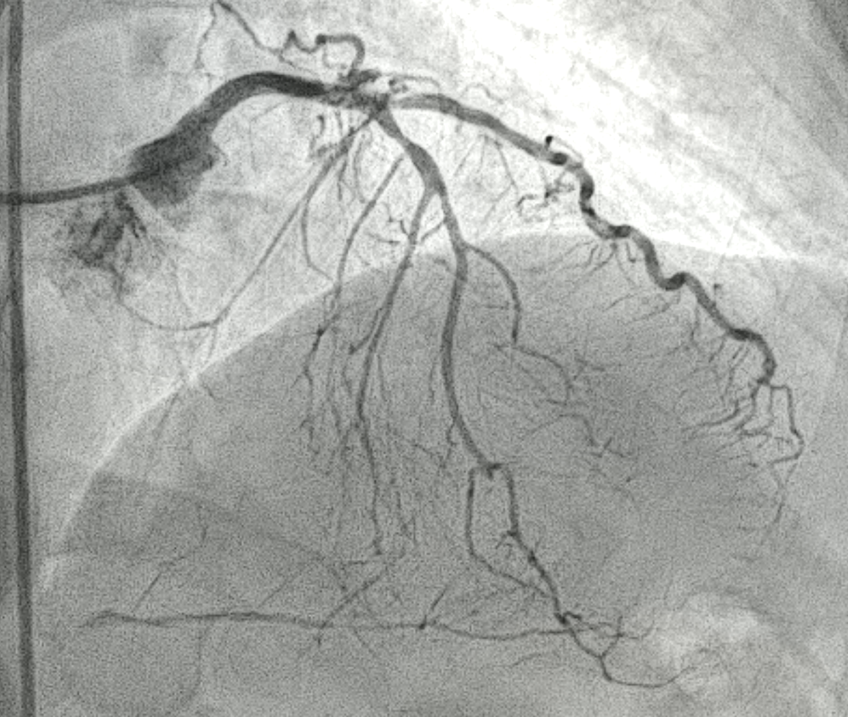

LM : patent

LAD: middle part 80% stenosis, sending collateral vessels to PDA and LCX

LCX: proximal part 90% stenosis, distal nearly total occlusion

RCA: proximal part 70% stenosis, middle nearly total occlusion